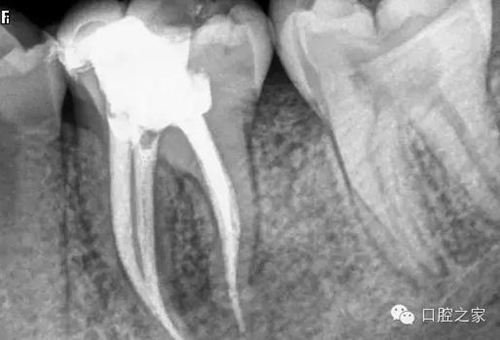

(4)根管欠填或超填 良好的根管充填是適填,無論是去髓術(shù)或根管治療,只要根管經(jīng)過有效的藥物消毒,允許少量欠填或超填(0.5~1.0㎜)。但如欠填過多,近根尖孔處形成死腔,可能導(dǎo)致組織液滯留,尤其是根尖周有炎癥者,帶有細(xì)菌的液體回流積聚,可繼續(xù)成為感染源,使根尖周病變難以愈合。而超填過多的牙膠尖難以被組織吸收,同樣會影響病變的愈合。

蘸一般藥液的棉捻或紙尖X 線片難以顯影,只有在根尖切除或拔除患牙后才能確診。但蘸有碘仿等X線阻射藥物的棉捻在照片上則易顯影(圖3)。此外,行樁冠修復(fù)的患牙,在釘?shù)李A(yù)備時如操作失誤,也可將牙膠尖推出根尖孔,導(dǎo)致治療失敗。